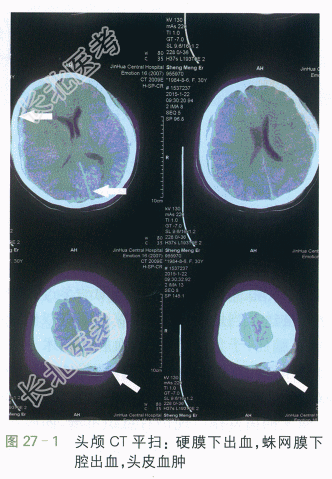

(2)影像学检查。头颅CT(术前):硬膜下出血,蛛网膜下腔出血,头皮血肿,如图27-1所示。头颅CT(术后):右侧额顶叶脑出血,右侧枕叶、双侧额叶、左侧颞叶及丘脑梗死灶考虑;蛛网膜下腔出血,如图27-2所示。